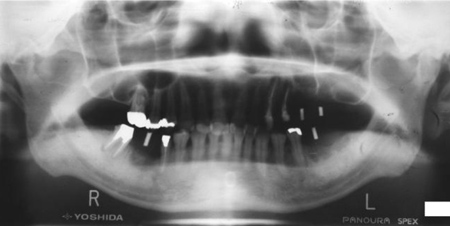

術前パノラマX線写真

術後レントゲン写真